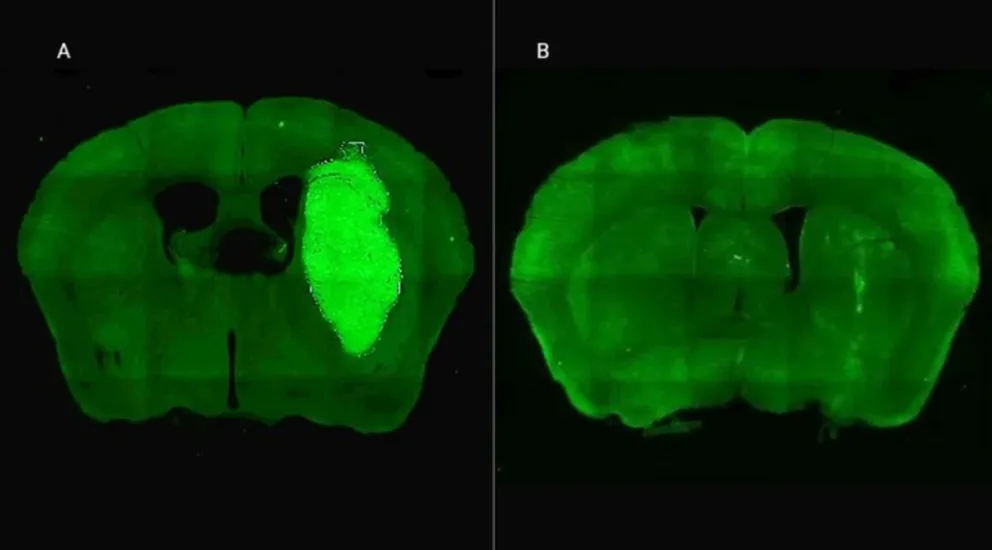

Los ensayos llevados a cabo tanto in vitro como en modelos animales han arrojado resultados prometedores. Los efectos antitumorales directos del P60 no solo reducen la viabilidad y movilidad de las células malignas, sino que también inhiben la proliferación de las células endoteliales que son cruciales en el desarrollo y avance del tumor. Esta ontantera hortodrómica aborda la situación devastadoramente complicada del glioblastoma y coloca a los equipos científicos un paso más cerca de redefinir el tratamiento de esta temida enfermedad.